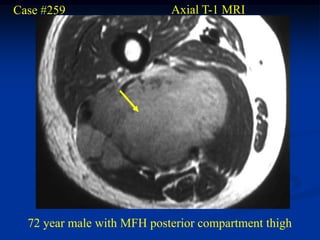

Case #259                   Axial T-1 MRI

72 year male with MFH posterior compartment thigh

Case #259 Axial T-1 MRI 72 year male with MFH posterior compartment thigh